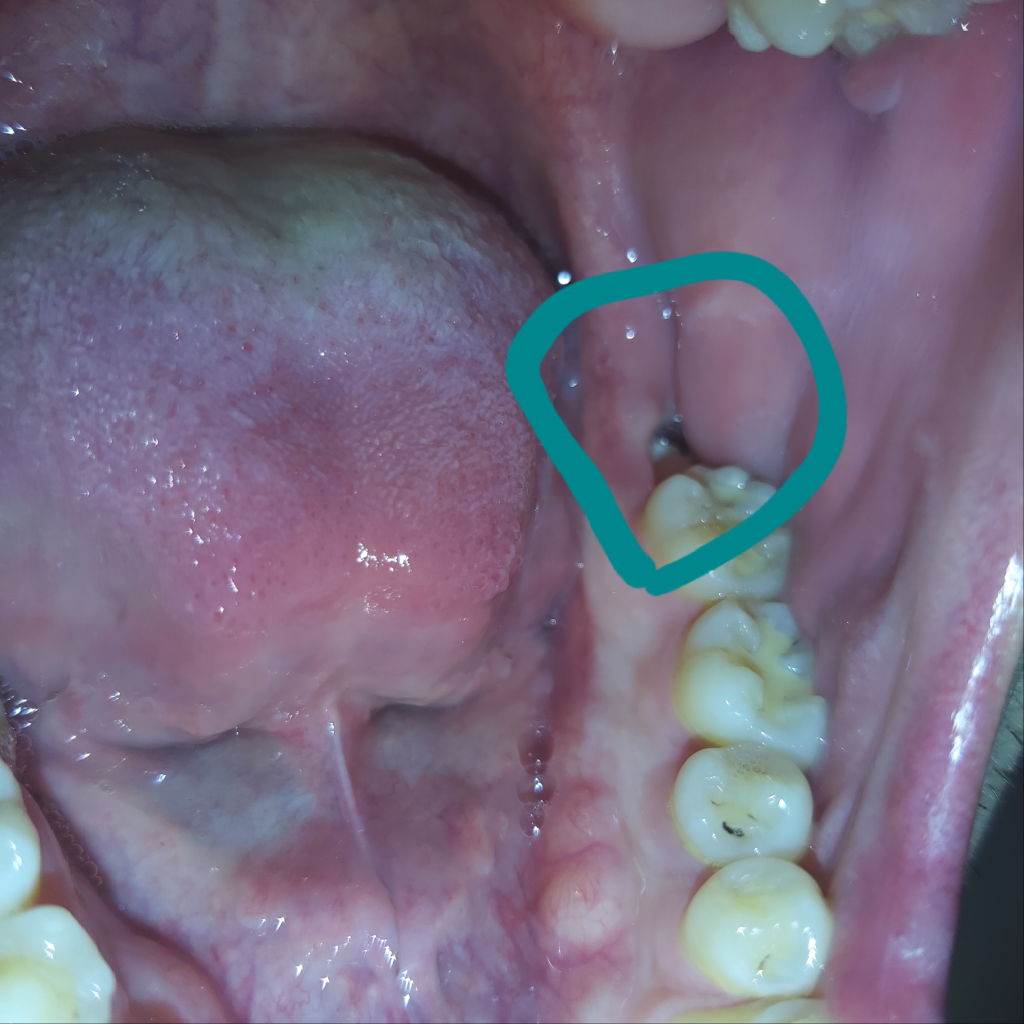

사랑니 발치 약 2주 뒤 주사기 가글 시 혈병 탈락..?

아래쪽 매복사랑니 발치 후 약 2주가 경과되었습니다. 발치부위에 음식물이 허옇게 낀 것 같아 주사기로 물을 쏴서 빼냈는데, 하얗게 되었던 부위 중 구멍이 살짝 뚫린 것 같이 빨간 상태로 변했습니다.

주사기 수압이 세서 치유부위가 떨어진 건지 궁금합니다ㅜ

피는 안나지만 기분탓인지 약간 욱신거리는 느낌입니다..

• 1번 째 사진